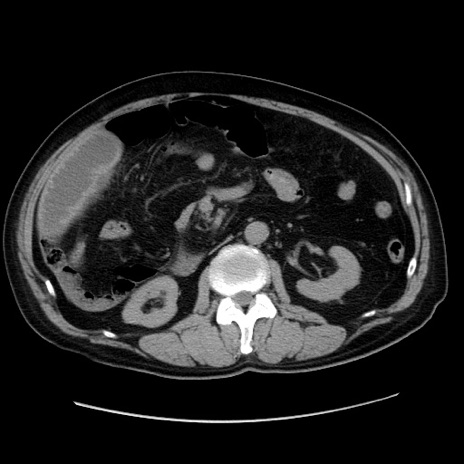

症例30(横断像)

【症例】80歳代男性

【主訴】臍周囲痛

【現病歴】約6時間前から臍下部痛が出現。次第に腹部膨隆・背部痛も生じてきたため来院。背部痛の場所は変化しない。

【身体所見】意識清明、BT 36.3℃、BP  131/87mmHg、P 87bpm、SpO2 100%(RA)、臍周囲自発痛・圧痛あり、反跳痛なし、自発痛部位に一致して板状硬あり、腹部膨隆、腸雑音減弱、CVA tenderness両側陰性。

【データ】WBC 19600、CRP 0.33